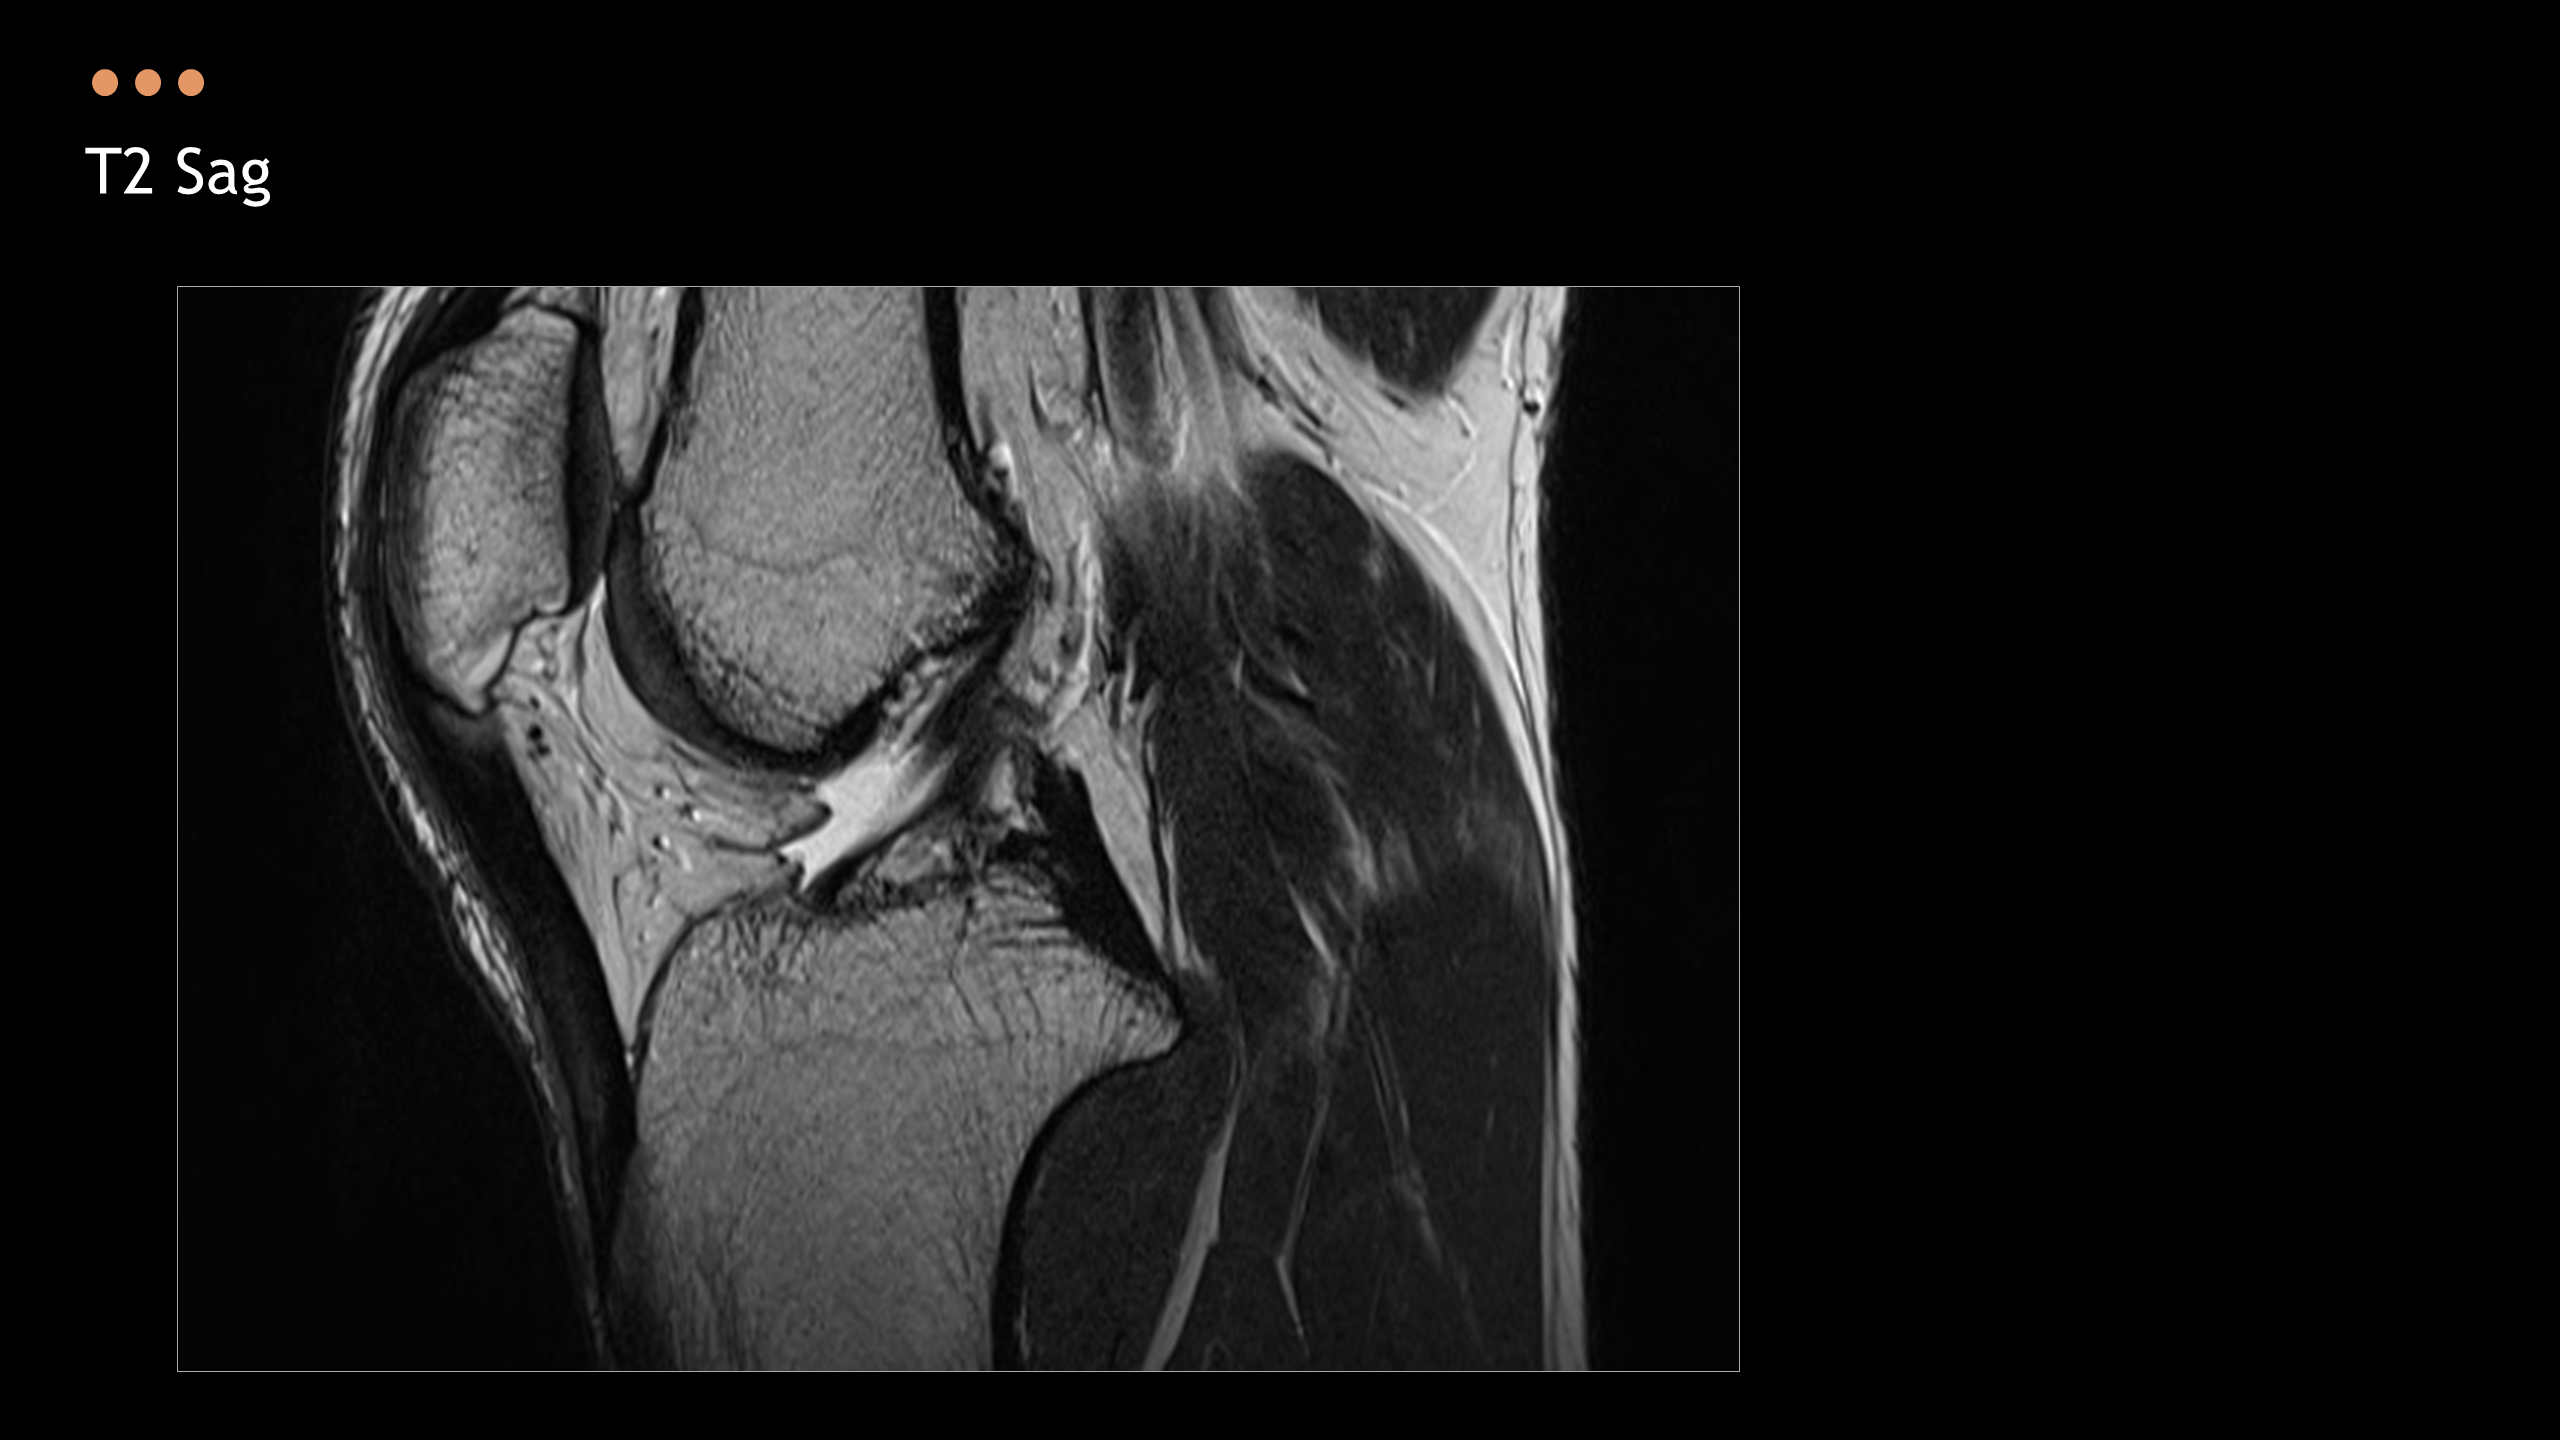

아래의 Normal Knee MR Anatomy를 숙지하고 오셔야, 강의에 어려움이 없습니다.